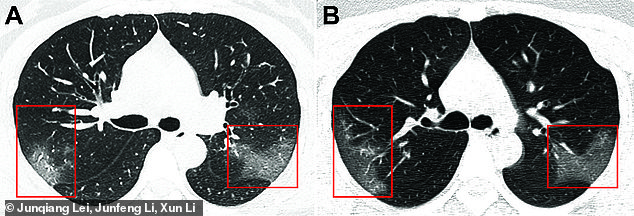

Skaneri i një 33-vjeçareje tregon efektin që ka krijuar koronavirusi i ri 2019-nCoV në mushkëritë e saj. Gruaja e cila kishte udhëtuar për në Lanzhou të Kinës mbërriti në spital me temperaturë të lartë, frymëmarrje të rënduar, pasi kishte pesë ditë me kollë të thatë. Mjekët e diagnostikuan atë me llojin e ri të koronavirusit pasi ajo kishte një numër të ulët të qelizave të gjakut, që përcaktonin infeksionin.

Skaneri tregon copëza të bardha në pjesën e poshtme të mushkërive, gjë që tregon atë që radiologët e quajnë mbushja e hapësirave të ajrit në mushkëri.

Pikat e bardha shfaqen më të theksuara në skanerin e dytë i cila është kryer tre ditë pasi u bë skaneri i parë dhe më pas trajtimi.

Imazhet u prezantuan nga një grup studiuesish në revistën Radialogy.

Radiologu Paras Lakhani nga Universiteti Thomas Jefferson, në Filadelfia i cili nuk ishte i përfshirë në studim, por ekzaminoi imazhet, tha: “Nëse do të zmadhojmë imazhin, pikat e bardha do të na duken si një xham i ngjitur në mushkëri, ndërsa në të ka diçka të lëngshme që mbush hapësirat e mushkërive”

Gruaja u trajtua duke përdorur një proteinë për të trajtuar infeksione virale të quajtur interferon. Sidoqoftë ajo vazhdon të jetë në gjendje të rëndë. Lakhari tha se pneumonia zakonisht mjekohet me antibiotikë dhe zakonisht gjendja e pacientit nuk përparon me shpejtësi. Pikat e bardha u identifikuan të ngjashme me SARS dhe MERS, të cilët janë gjithashtu koronaviruse.

Radiologu tha se skanimi i atyre viruseve ka karakteristika të ngjashme me atë të 33 vjeçarit në Wuhan. Sidoqoftë, mënyra më e mirë për të identifikuar koronavirusin është testimi i pështymës së pacienteve, edhe pse prova më efektive është kur pacienti tregon simptoma./Daily Mail/